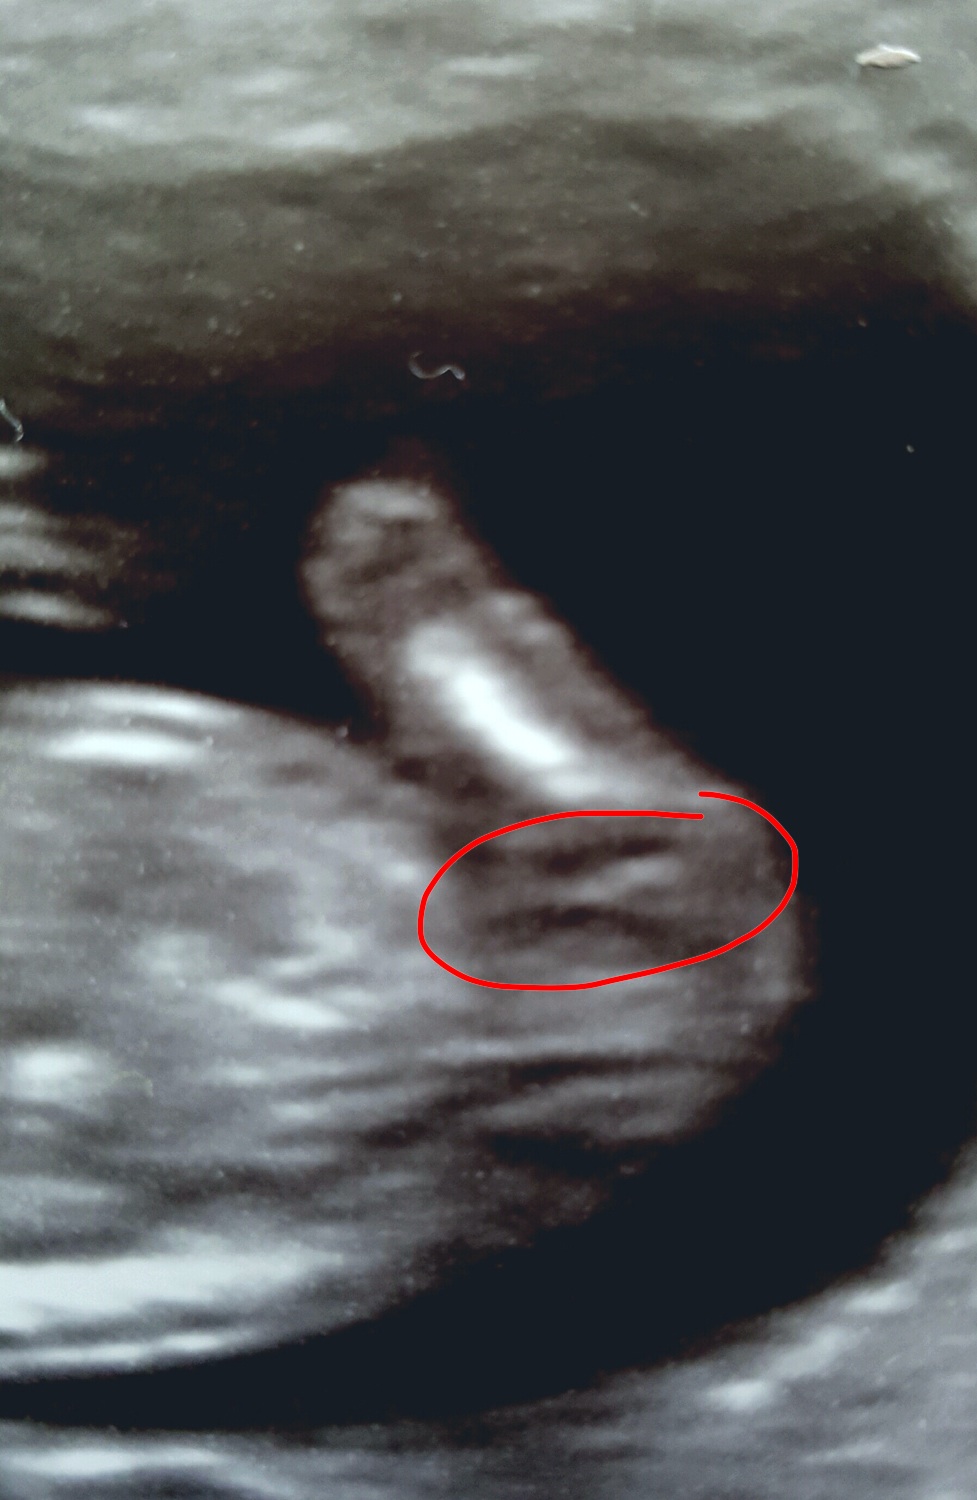

Is this even the nub?

With my last baby I had a clear nub shot, which was blatantly obvious to everyone here and you all guessed correctly! This time I thought I caught a glance of a nub on screen, but I'm not sure if it's even been captured in the only scan photo I have. Is what I've circled even the nub, or just a random shape? I was 13 weeks by LMP but measured 12+1. Thanks

That is in fact your nub! measuring 12/1 It could still go either way

I think this may possibly turn to boy as its looking stacked.

Thanks. I've been told elsewhere that it's not the nub, and also that it's early but girly! Think where you see stacking they see a fork. Looks like it's anybodies guess then!

it appears to stack because the top is thicker but it could be interference. Fork is definitely there but at this stage still under development and will stay or change.

I'm going to say early but girly.

I'm guessing girl as its flat. It is a bit difficult to see if it's stacked or forked but guessing forked.